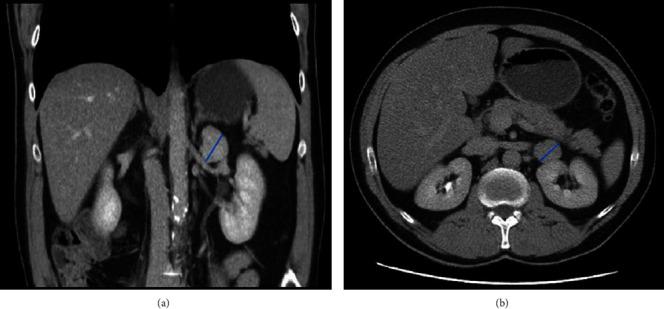

A solitary fibrous tumor develops from mesenchymal cells as a pleural neoplasm, but it is also occasionally reported in extrapleural sites. Retroperitoneal tumors are a group of neoplasms located between muscles and the fascia of the posterior abdominal wall and the parietal peritoneum. Their cytology differs from that of urinary tract organs or adrenals. This case report presents a rare solitary fibrous tumor incidentally found during an ultrasound examination. A 54-year-old male underwent urgent surgery for a tumor located in the left retroperitoneal space. The histologic examination confirmed a solitary fibrous tumor with a 5% Ki67 proliferation index, a 1 MF/10 HPF mitotic activity, and CD34-positive immunostains. A solitary fibrous tumor is a rare retroperitoneal tumor. Its symptoms and signs might resemble those of the classical triad of renal cell carcinoma, although the tumor's growth phase is typically asymptomatic. Intraoperative diagnosis of a solitary fibrous tumor strongly recommends radical excision.